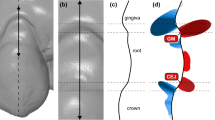

Surface curvature is the quantity that measures how much the surface locally at each point deviates from the plane orthogonal to the surface at that point (called the tangent plane). The amount of deviation depends on the direction we choose in the tangent plane. The two directions where the amount of change is minimum and maximum are called principal curvature directions, and they correspond to the principal curvatures, i.e., maximum curvature kmax and minimum curvature kmin (Fig. 1). These two principal curvatures are eigenvalues of the shape operator [30] and can be combined in several ways to obtain a quantity representing a curvature measure [31], e.g.,

Concept of surface curvature estimation displayed on an intraoral scan (a). With a surface curvature estimation algorithm, principal curvature directions and values, i.e., maximum (kmax) and minimum (kmin), were computed for each point of the intraoral scan. Principal curvature directions for a selected point (i.e., the intersection of the white lines) of two anatomically different regions, i.e., central (B) and interdental (C), were displayed with corresponding cross-sections (b and c). The principal curvature directions coincide with corono-apical (full white line) and mesio-distal (dashed white line) directions in those two selected regions. Note that principal curvature directions are switched in central and interdental regions. The curvature value of each point’s surface is visualised with colour mapping (d)

Central and interdental gingiva are two distinct regions regarding their shape, affecting the selection of optimal curvature measures. The shape of the central gingiva mainly depends on the tooth’s position in the dental arch, the position of the root in relation to the alveolar process, and the anatomy of the root [48]. Those relations are typically displayed as a mesial-distal convexity of central gingival as observed with a mesial-distal cross-section of a maxillary canine (Fig. 1b) and colour-coded curvature maps using Max (Additional file 1: Fig. 1). In the absence of pathology, the central gingiva is tightly adapted to the underlying hard tissues with a knife-edge margin, i.e., observing the coronal-apical profile [48]. With gingival inflammation, swelling occurs, additionally and reliably displayed with Min (Fig. 5a). In contrast, the shape of the interdental gingiva is more complex. It depends on the contour of the proximal tooth surfaces, underlying bone support, and gingival embrasures’ size, shape, and location [48]. As the bone support of two neighbouring teeth may differ, interdental ROI was not further divided into mesial and distal ROI. Observing cross-sections at the interdental gingiva revealed that principal curvatures are contrarywise as with central gingiva and are more similar regarding values (Fig. 1b and c). Therefore, combining both principal curvatures, such as MC, seems better to describe the swollen interdental gingiva (Fig. 5b). However, the analysis with its parameters and clinical relevance needs to be further tested for specific clinical scenarios and datasets to enable practical quantitative gingival shape analysis using optical scans.